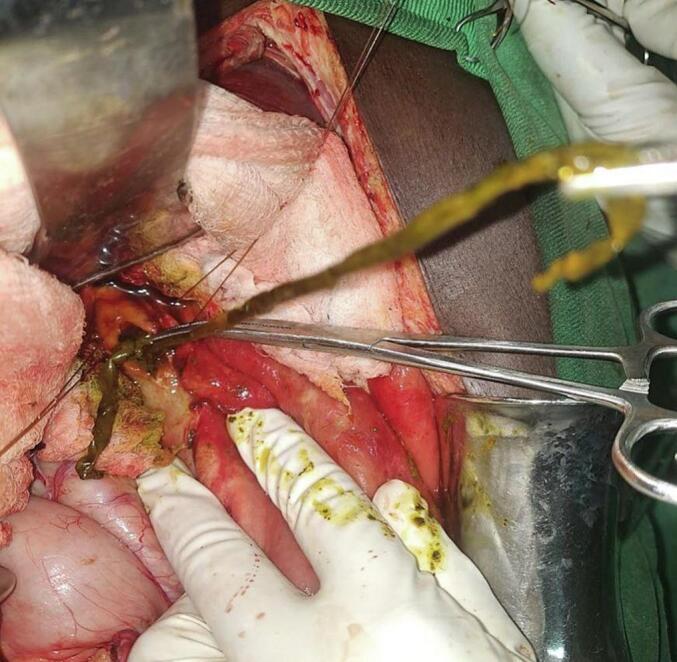

CASE PRESENTATION

A 28-year-old female farmer from a rural area presented with a one-year history of intermittent right upper quadrant pain, worsened by fatty meals. Her symptoms progressed a week before presentation to include fever, jaundice, dark urine, and pruritus. Examination revealed a positive Murphy sign and jaundice, with laboratory results showing leukocytosis and elevated bilirubin. Imaging confirmed biliary ascariasis with choledocholithiasis and ascending cholangitis. Intraoperatively, a sealed perforation of the gallbladder was found alongside a dead Ascaris and multiple stones in the common bile duct (CBD). Surgical intervention included removal of the worms and stones, cholecystectomy and CBD irrigation. Postoperative recovery was uneventful, and the patient was discharged with antihelminthic therapy.

一名来自农村地区的28岁女性农民,有一年间歇性右上腹疼痛病史,油腻餐后加重。在就诊前一周,她的症状进展,出现发热、黄疸、深色尿和瘙痒。检查发现墨菲氏征阳性和黄疸,实验室检查结果显示白细胞增多和胆红素升高。影像学检查证实为胆道蛔虫病合并胆总管结石和化脓性胆管炎。术中发现胆囊有一处封闭性穿孔,同时在胆总管内有一条死蛔虫和多个结石。手术干预包括取出蛔虫和结石、胆囊切除术及胆总管冲洗。术后恢复顺利,患者接受抗蠕虫治疗后出院。